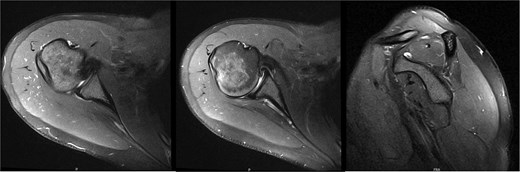

An 18-year-old, right-hand dominant woman presented reporting several weeks of right shoulder pain limiting participation in DIII collegiate volleyball. Examination revealed atrophy of the infraspinatus region. Muscle testing revealed weakness of infraspinatus and supraspinatus with reproducible symptoms. Radiographs were without transverse scapular ligament calcification (Fig. 1). Magnetic resonance imaging (MRI) arthrogram revealed low-grade undersurface fraying of the supraspinatus and infraspinatus tendons consistent with impingement, hypertrophic posterior inferior labrum, and no evidence of paralabral cyst (Fig. 2). Rest from hitting activities, anti-inflammatory medications, and periscapular strengthening therapy were initiated.

Initial MRI arthrogram revealed low-grade undersurface fraying of the supraspinatus and infraspinatus tendons consistent with internal impingement, hypertrophic posterior inferior labrum without visible tearing, and no evidence of paralabral cyst.